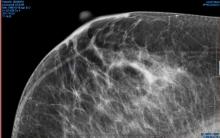

On the same day that Wisconsin state representatives introduced a new bill mandating patient notification of breast density, both chambers of Congress revived the national Breast Density and Mammography Reporting Act which was first drafted in 2013.

iCAD Inc. announced that its PowerLook Tomo Detection has been named 2017 Product of the Year by the New Hampshire High Technology Council, a member-driven organization with a focus on advancing innovation throughout the State of New Hampshire.  Built on deep learning technology, PowerLook Tomo Detection is the first and only concurrent-read cancer detection solution for digital breast tomosynthesis (DBT), according to the company, engineered to make it possible for radiologists to detect breast cancer more efficiently.